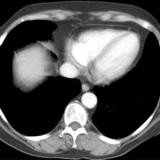

Part'l absc peric CT